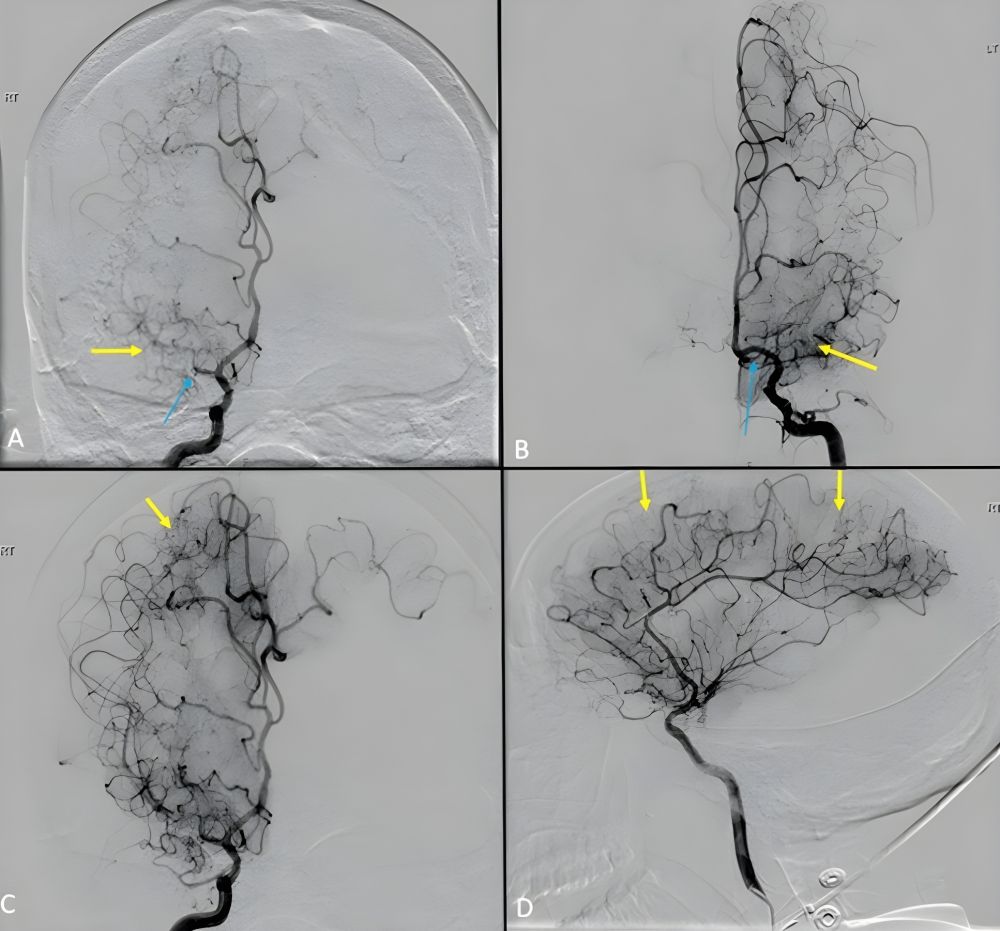

Hình 2. Chụp mạch máu số hoá xoá nền (DSA) với hẹp tắt động mạch não giữa đoạn M1 (mũi tên xanh) bên phải (A), bên trái (B) và các mạch máu Moyamoya (mũi tên vàng)

Bệnh Moyamoya là một bệnh lý mạch máu não hiếm gặp, đặc trưng bởi sự hẹp dần hoặc tắc nghẽn của các nhánh chính trong não, đặc biệt là động mạch cảnh trong và các nhánh của vòng Willis.

Khi những mạch máu lớn này bị tắc, cơ thể cố gắng tự tạo ra những mạch máu nhỏ li ti để bù trừ lưu lượng máu não — nhìn trên phim chụp mạch, chúng hiện lên như “làn khói mờ”, và từ đó, bệnh được người Nhật đặt tên là Moyamoya (nghĩa là “hơi khói”).